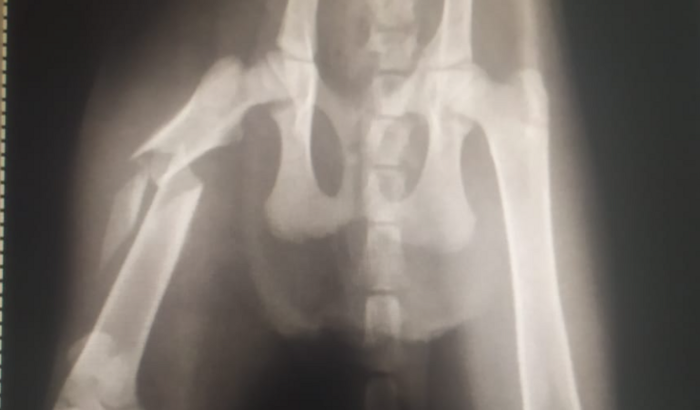

olá amiguinhos, sou shelda uma gatinha de 4 meses. Sofri maus tratos, fui arremessada de um carro dentro de um mato para morrer. Na queda fraturei meu femur. Preciso de uma cirurgia urgente pois corro risco de perder minha perninha. Valor 2.500 reais em média. PIX maria.jududa@hotmail.com por favor me ajudem